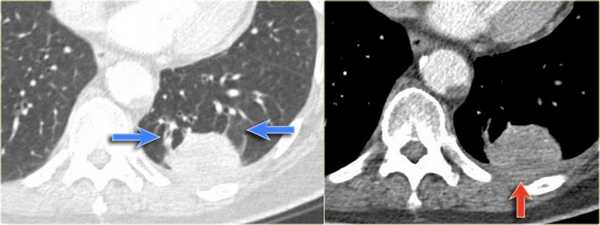

На боковой рентгенограмме выявляется образование, которое исходит из плевры. На первый взгляд — это образование, исходящее из плевры.

Далее перейдите к оценки КТ-снимков.

На КТ четко выявлено, что это образование легкого. Для многих данные изменения на КТ заставили бы задуматься о раке легкого. Красной стрелкой указана утолщение плевры, а синими стрелками указаны сосуды вокруг данного образования, что называют хвостом кометы.

Всякий раз, когда встречается образование, сочлененное с плеврой, а также похожее на рак легкого, то не забудьте об округлом ателектазе.

Округлый ателектаз — это доброкачественные изменения, которые на последующих снимках не изменяются в размерах и чаще встречаются у пациентов, которые имели контакт с асбестом.

В левой нижней доле визуализируются изменения высокой плотности. На фронтальной рентгенограмме данное образование выглядит схоже с консолидацией так, как на боковой границы острые, то скорее это образование. Красной стрелкой указано утолщение плевры.

Несмотря на то, что легочный рак находится на вершине нашего дифференциального ряда, данные изменения характерны для округлого ателектаза, что хорошо визуализируется на КТ (утолщение плевры, овальная форма, симптом хвоста кометы).